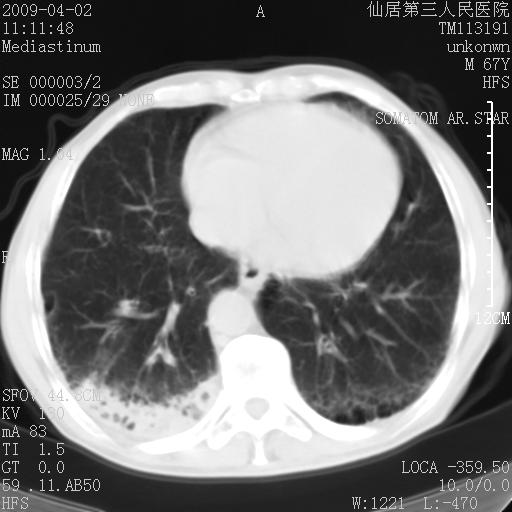

患者老年男性,乏力畏寒来诊,摄胸片示右下肺感染性病变,抗炎两周后复查胸片,无好转有进展。

后做ct平扫表现如下:

考虑右肺炎症可能性大,不除外细支气管肺泡癌

是否还要考虑肺间质纤维化,建议hrct扫描。

病灶呈蜂窝征,纵隔多个淋巴结肿大;肺泡癌需考虑

我认为普通的感染应该可以除外,间质性肺炎可能性较大,但如何解释纵膈的淋巴结肿大呢

考虑双肺间质性改变(间质纤维化?)伴右肺下叶感染。

支持11楼,考虑肺结核.年䶨;大,抗炎无效.纵隔淋巴结肿大.老年人下肺结核要警提